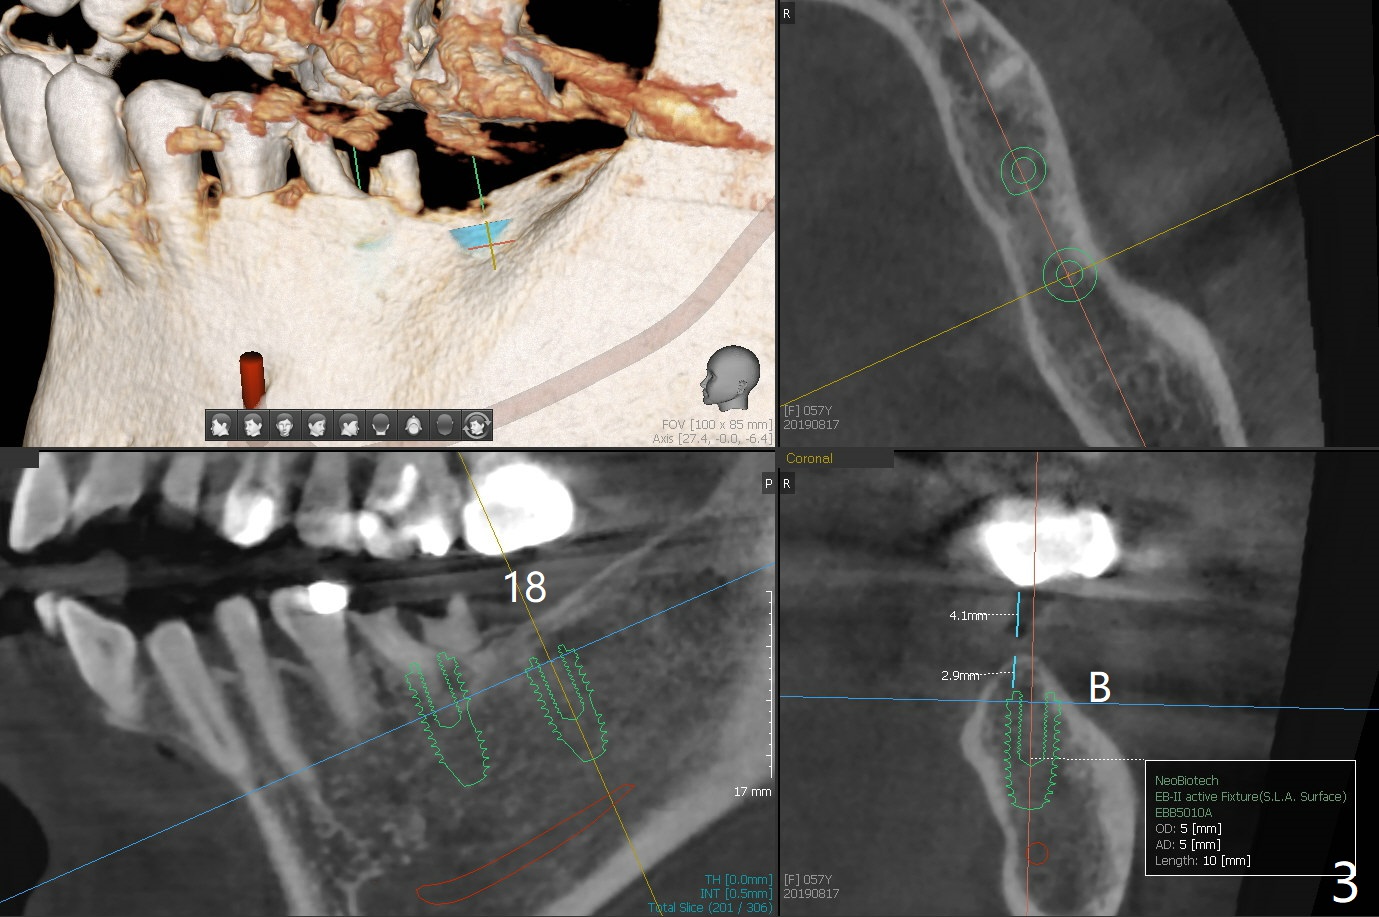

A 57-year-old woman agrees to have implants at #18 and 19 (Fig.1). Since the tooth #15 is supraerupted and there is limited vertical space at #18 (Fig.3), Magicore and FC will be placed at #18 and 19, respectively (Fig.3,2).